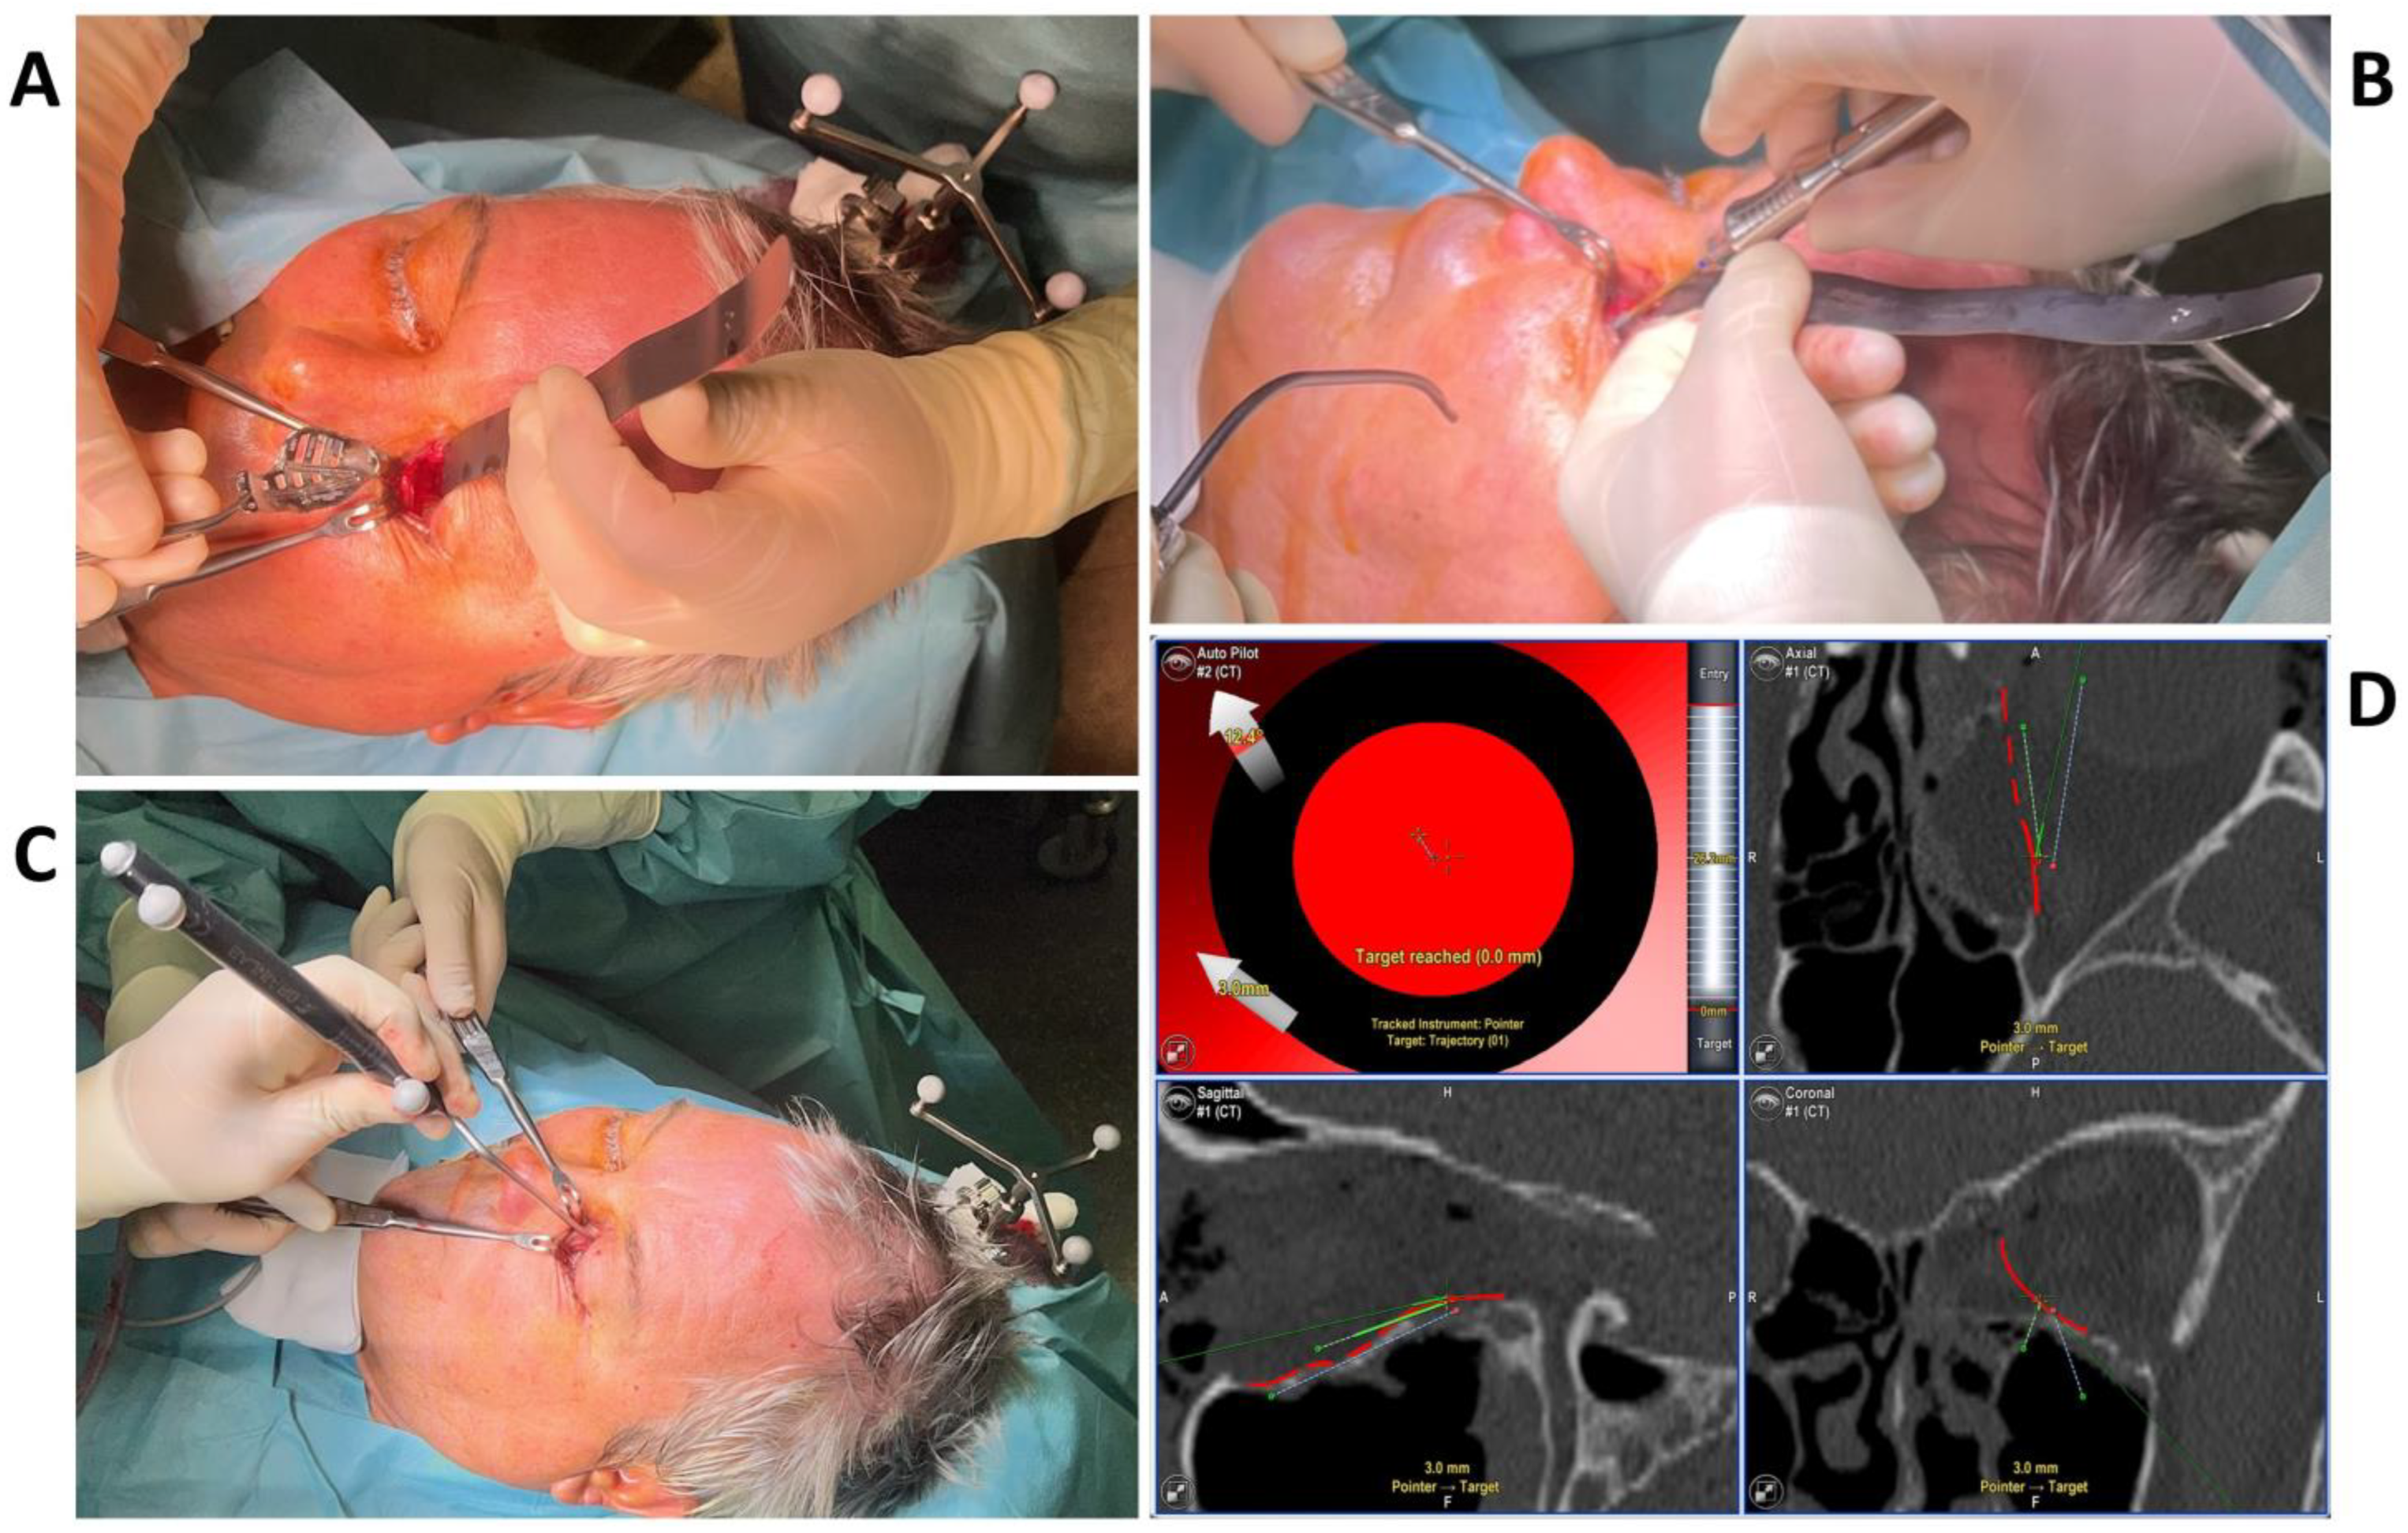

2.2. Surgery